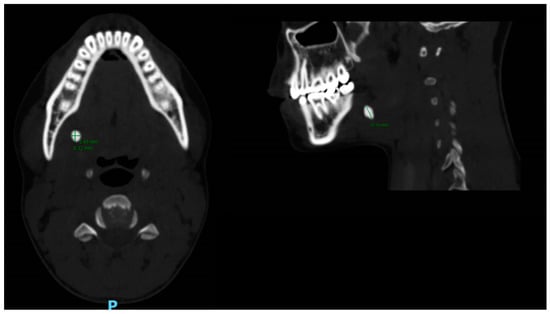

- Sialolith characteristics (according to CT)

- Size (Figure 1): length; width; height; volume (calculated by: length X width X height, we used the formula for a volume of a box as an approximation for the volume of the irregularly shaped sialoliths).

| Size(mm); | |

| Anterior-posterior (mean, SD) | 6.6 ± 4.2 |

| Superior-inferior (mean, SD) | 7.4 ± 4.6 |

| Lateral-lateral (mean, SD) | 5.2 ± 2.8 |

| Sialolith location (%); | |

| Gland | 12 |

| Hillus | 44 |

| Ductal | 27 |

| Papilla | 17 |